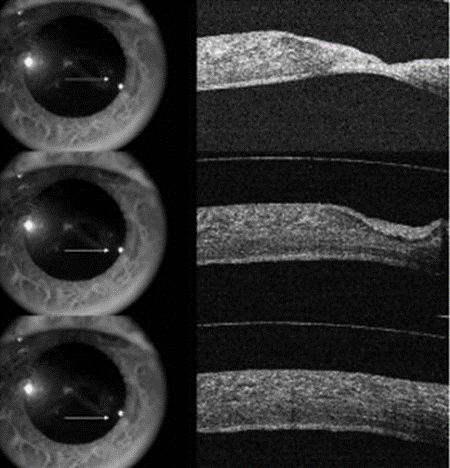

Figura 2. La imagen superior muestra el descemetocele (área señalada por las flechas) y el defecto epitelial. En la mitad y en la parte inferior, se aprecia la adaptación del lente escleral mostrando la evolución de la reepitelización y la recuperación del descemetocele.6